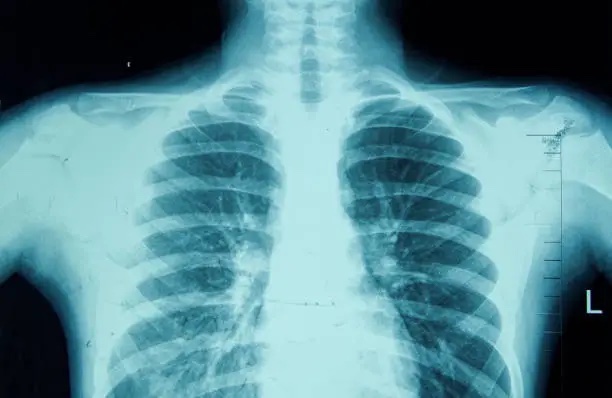

Cathy Beesey reflects on a harrowing medical experience involving fear and uncertainty following an X-ray suggesting cancer. Ultimately diagnosed with an autoimmune disorder, she draws inspiration from a writing group to process her emotions and experiences.